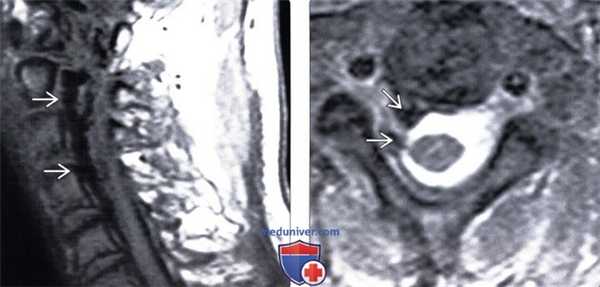

• Для подтверждения диагноза и выбора метода лечения применяется селективная артериография позвоночника(Слева) Сагиттальный срез, Т2-ВИ, пациент с фистулой 1 типа: диффузная гиперинтенсивность сигнала грудного отдела спинного мозга при относительном сохранении нормальной интенсивности его периферии. Сосудистые полости вдоль задней поверхности спинного мозга не видны.

• Обращайте внимание на небольшие размеры и нечеткие границы нижней полой вены или металлический артефакт в проекции НПВ (кава-фильтр)(Слева) Сагиттальный срез, Т2-ВИ: типичная картина отека спинного мозга на фоне спинальной дуральной фистулы в виде гиперинтенсивности Т2-сигнала центральных отделов спинного мозга и множественных сосудистых пустот на его поверхности.

• Истинная артериовенозная фистула, нет промежуточной сети из мелких сосудов(Слева) Аксиальный срез, Т2-ВИ, пациенте дАВФ 7 типа: изменение Т2-сигнала спинного мозга в виде гиперинтенсивности центральной зоны и сохранением периферии. Спинной мозг окружен слоем СМЖ, однако сосудистых пустот при этом не видно.

(Справа) Сагиттальный срез, FS Т1 -ВИ с КУ: невыраженная зазубренность дорзальной поверхности спинного мозга, связанная в данном случае (пациент с фистулой 7 типа) с минимальным контрастированием сосудов. Явных признаков контрастного усиления сигнала спинного мозга нет. Отсутствие контрастирования спинного мозга не исключает наличие фистулы. (Слева) На фронтальной реконструкции динамической контрастной МР-ангиографии фистула локализована в области неврального отверстия BE, шунтирование крови осуществляется в расширенные интрадуральные вены.